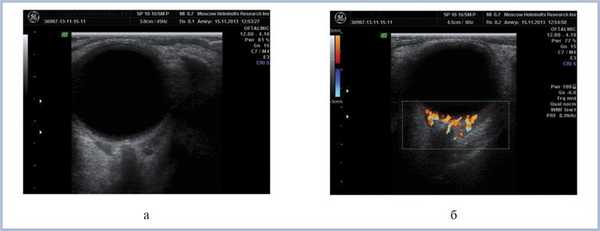

В настоящее время, спустя 6 мес после постановки диагноза и проведения 4 курсов ПХТ, состояние больного удовлетворительное. Патологических изменений со стороны ЦНС и других систем органов на данный момент не выявлено. Зрение обоих глаз с миопической коррекцией 1,0. Клинически отмечается положительная динамика в виде уплощения и уменьшения площади поражения (рис. 7, 8). Аналогичные результаты демонстрируют и инструментальные методы исследования (рис. 9). Однако в связи с наличием остаточного опухолевого процесса больной был направлен к гематологам для продолжения курса лечения (ПХТ).

Рис. 7. Офтальмоскопическая картина (а) и флюоресцентная ангиограмма (б) глазного дна левого глаза через 6 мес после ПХТ. Отмечается уплощение очага и уменьшение ретинального отека.

Рис. 8. Офтальмоскопическая картина (а) и флюоресцентная ангиограмма (б) глазного дна правого глаза через 6 мес после ПХТ.

Рис. 9. Дуплексное сканирование левого глаза и орбиты через 6 мес после ПХТ. Определяется уменьшение размеров опухолевой ткани в В-режиме (а), сохранность собственной васкуляризации в режиме ЦДК (б).